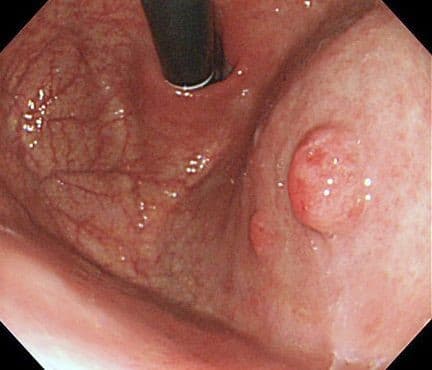

Эндоскопически они обычно гладкие, куполообразные (0-Is, 0-Isp тип), размерами от 5 до 15 мм в диаметре, хотя могут быть намного больше. Большие полипы становятся дольчатыми, расположенными на ножке (0-Ip тип), поверхность эпителия полипа нередко эрозирована, что может являться причиной хронической кровопотери и железодефицитной анемии. Редко поступают пациенты с признаками высокой непроходимости, вследствие обтурации или пролабирования полипа через привратник. Гиперпластические полипы возникают как гиперпролиферативный ответ на повреждение слизистой (эрозии, язвы). Длительное химическое воздействие соляной кислоты и наличие инфекции H.pylori могут быть первоначальной ступенью в их развитии.

Гистологическая характеристика включает удлиненные, искаженные, разветвленные, дилятированные фовеолярные железы с богато васкуляризованной стромой на фоне хронического воспаления. Показано, что в 1 - 20 % полипов могут скрываться фокусы диспластических изменений. В целом, распространенность очага карциномы составляет менее 2 % и, как правило, в полипах размерами более 20 мм. В связи с потенциальным риском развития рака желудка, все гиперпластические полипы более 10 мм в диаметре следует полностью удалять. Резекция полиповидных образований всегда должна быть дополнена взятием образцов интактной слизистой, которые содержат информацию о распространенности и тяжести воспалительных и атрофических изменений в окружающей слизистой оболочке (по морфологической классификации OLGA). В результате - определяется стратификация риска развития рака желудка.